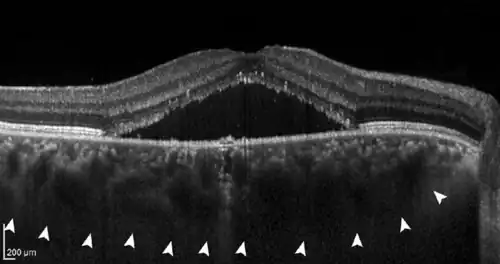

The disease mechanisms are not completely understood. All pachychoroid disorders of the macula show choroidal thickening and congestion with increased blood vessel diameter, especially in the deep choroid (the so-called Haller's layer). This results in increased pressure from the deep choroid against the superficial choroid close to the retina, damaging the fine blood vessels (capillaries) needed to supply oxygen and nutrients to the retinal pigment epithelium and retina. Additionally, fluid can leak from these damaged vessels and accumulate under the retina.[1][2]

- If further damage to Bruch's membrane and the pigment epithelium causes fluid to accumulate under the retina, central serous chorioretinopathy (CSC) develops. In this stage, patients often have blurred vision and report a reduction in visual acuity with perception of a central "grey spot". In the majority of patients, spontaneous resolution of the subretinal fluid occurs within a few months, but recurs in up to 50% of cases. In some patients the fluid remains, making it a chronic disease; medical therapy or the application of various laser methods is possible.